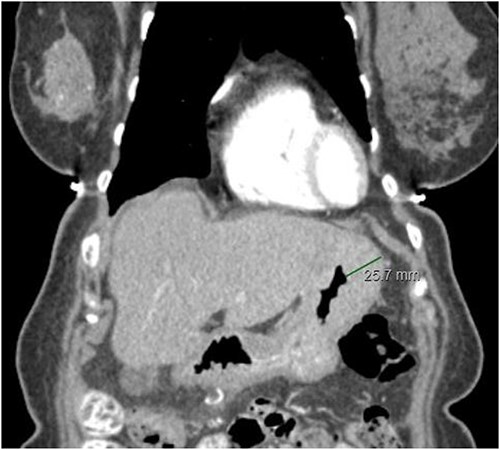

The staging work-up was done based upon the national comprehensive cancer network (NCCN) guidelines. A Computed tomography (CT) scan of the abdomen and pelvis was done which showed minimal ascites. There was also evidence of prominence of the stomach wall near the fundus, with thickness measuring 2.2 cm in the CT scan (Fig. 2). This led to an endoscopic gastroduodenoscopy (EGD) that showed a mass in the fundus. Biopsy of the mass revealed lobular carcinoma of the stomach. Bone scan and magnetic resonance imaging (MRI) brain was negative. There was no liver metastasis.

CT abdomen/pelvis displaying gastric wall thickening, coronal view.